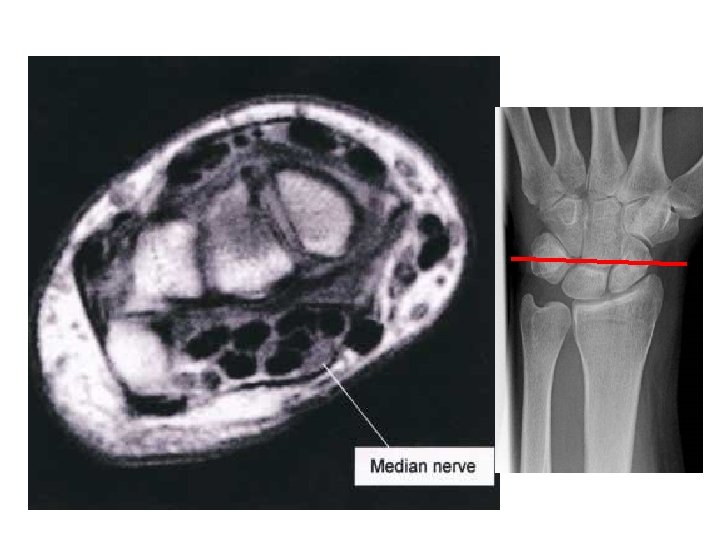

MRI

HAND

X RAY